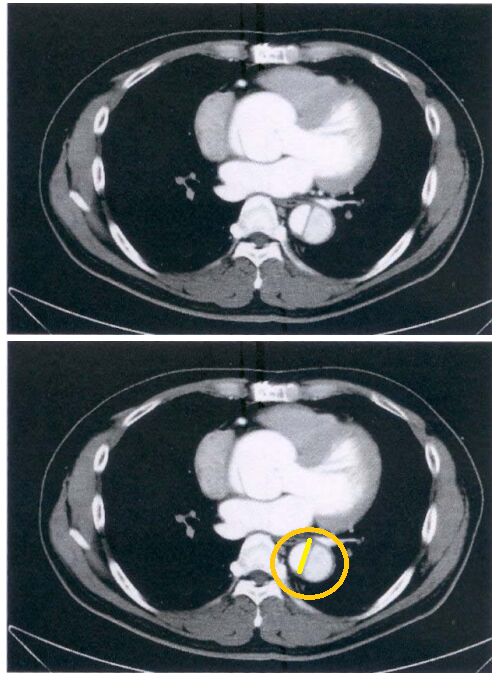

75 76 歲男性主訴胸悶及呼吸困難,注射對比劑後 CT 影像如附圖,則最可能的診斷為下列何者?

圈起來的部分,很典型的主動脈剝離